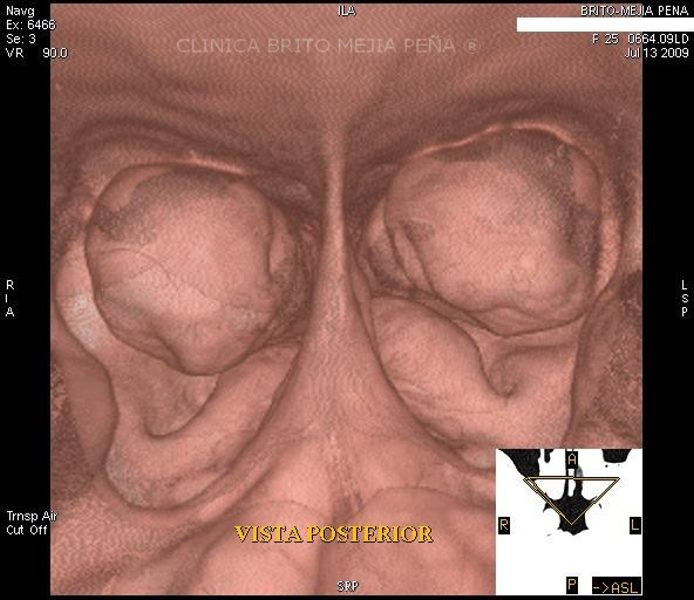

Fx piso órbita y hernia musculo

Fx piso órbita y hernia músculo sagital